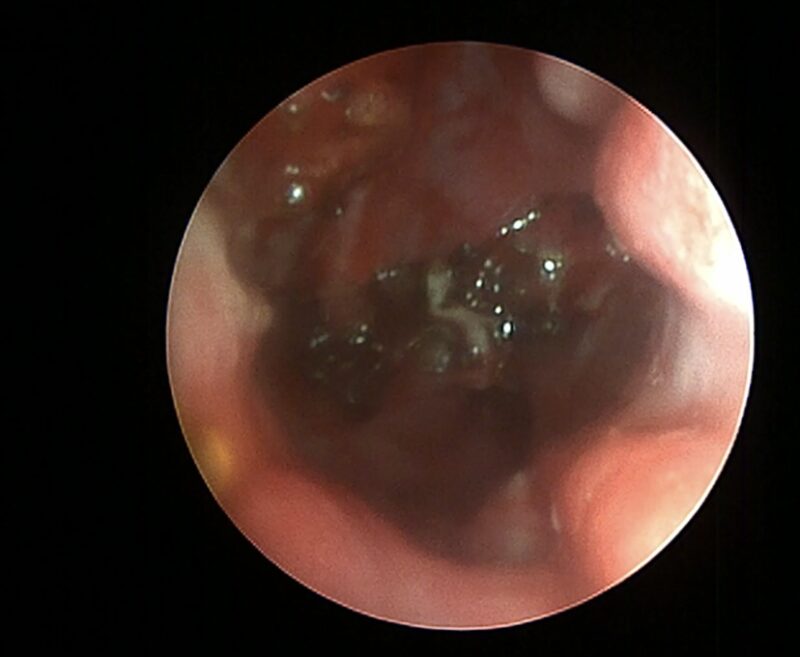

Die geringe Eindringtiefe und minimale kollaterale Hitzeeinwirkung der 1470 nm Laserstrahlen erlaubt auch deren Verwendung in den oberen Atemwegen und im Pharynx von Katzen und Hunden (Abb. 3).